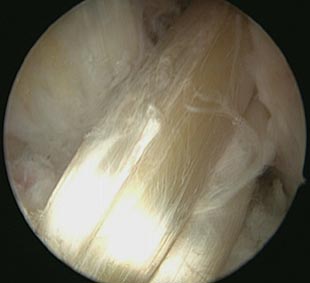

Nach ausgiebigem Testen des eingebrachten Transplantats auf seine Festigkeit, wird dessen unteres Ende, das noch im Bohrkanal des Unterschenkels liegt, mit einer resorbierbaren Schraube fixiert. Nach erneuter intraartikulärer Prüfung des Transplantats erfolgt der Wundverschluss und somit das Ende der Operation.